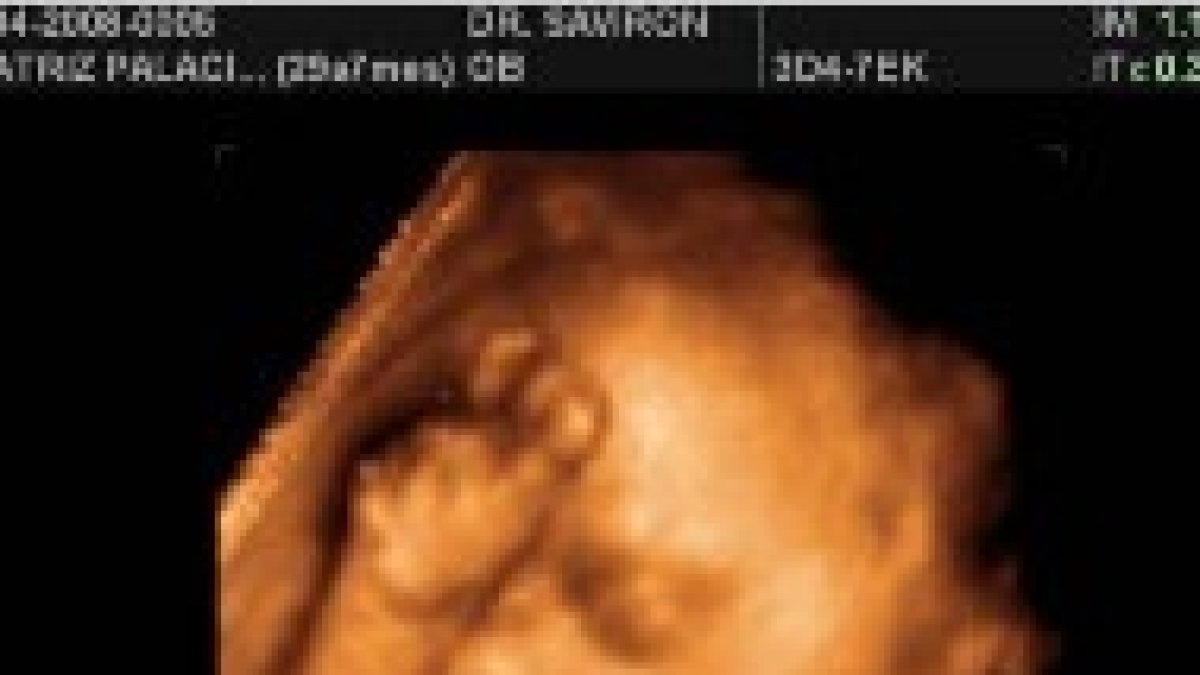

Ecografía en 3D de un feto

La ley señala que un médico debe realizar un ultrasonido 24 horas antes de un aborto, excepto en casos de emergencia médica, y mostrar la imagen a la madre, haciéndole escuchar los latidos del corazón del feto. Sin embargo, la mujer puede optar por no ver la imagen o escuchar los latidos. Para ello deberá firmar una declaración antes de que se le realice el sonograma.